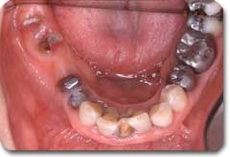

かみ合わせ治療前の状態です

かみ合わせ治療によりここまで治すことができます